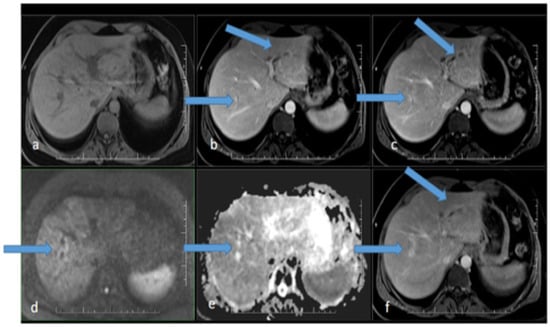

Ultrasonography showed hepatomegaly and intrahepatic biliary duct dilation with focal, irregular wall thickening. There were no signs of extrahepatic biliary obstruction. MR cholangiography clarified several strictures of the intrahepatic ducts with apparent post-stenotic dilatations in both liver lobes, more significant on the right side. Dilatation of the extrahepatic ducts was again not present (Figure 1).

Figure 1. MR scan of the liver before the initiation of antibiotic therapy: (a) native image; (b) arterial phase; (c) venous phase; (d) diffusion-weighted imaging; (e) ADC map; (f) delayed phase. Apparent focal dilatation of the intrahepatic bile ducts is marked with arrows in the left and right lobes in the arterial (b), venous (c), and delayed phases, showing gradual opacification of the duct walls and peribiliary spaces, respectively. Increased signal in the duct wall area is indicated in diffusion-weighted imaging (d), with an iso-signal in the ADC map (e).